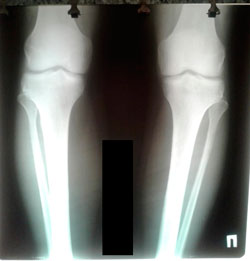

Исходник - 29 лет.

Дата операции - 29.09.2020

Дата снятия аппаратов 12.01.2021